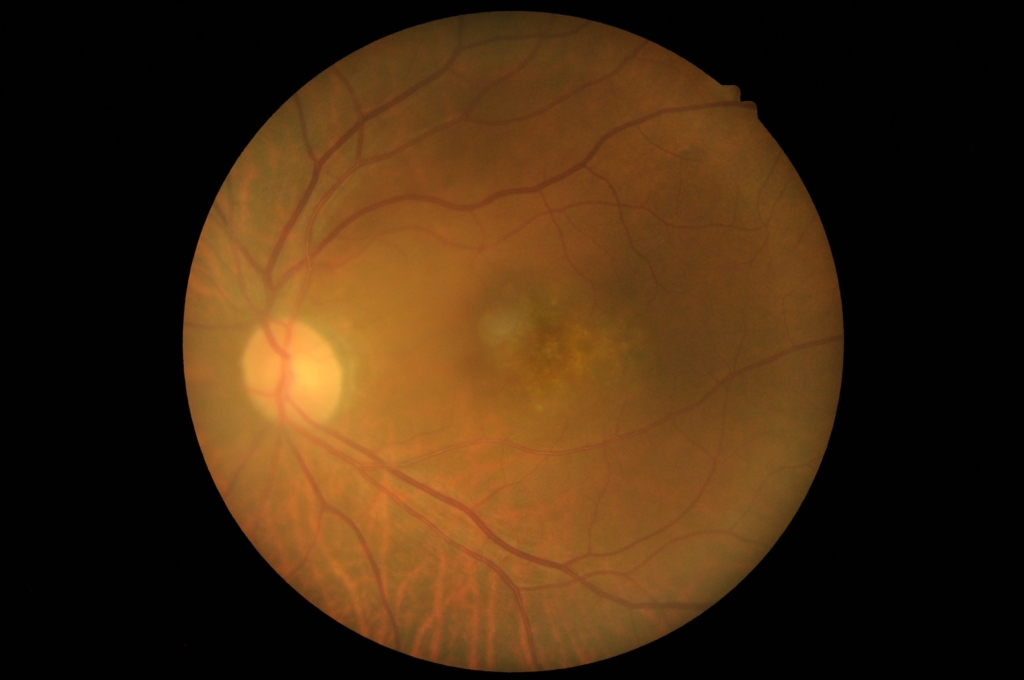

中心窩に灰白色病変がみられる。

網膜色素上皮 RPE異常の部位で、低~軽度高蛍光を示す。

黄斑に、IAでCNVの網目状の血管がみられる。

FAでびまん性に漏出がみられる。